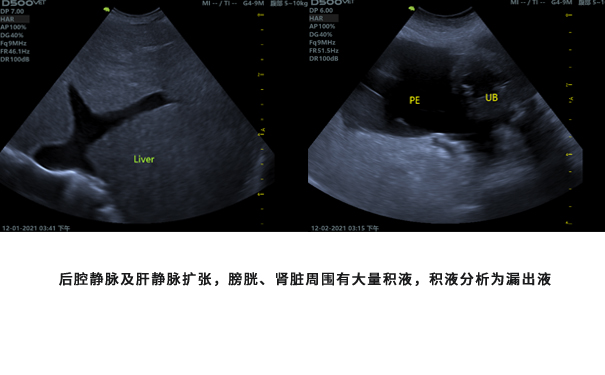

右心衰时右心房扩大时右心房压力约为15mmHg,由三尖瓣返流速度计算出PASP(收缩期肺动脉压力)为77.7mmHg;根据PREnd Vmax 2.1 m/s 计算出PADP为32.6mmHg;

抽腹腔积液